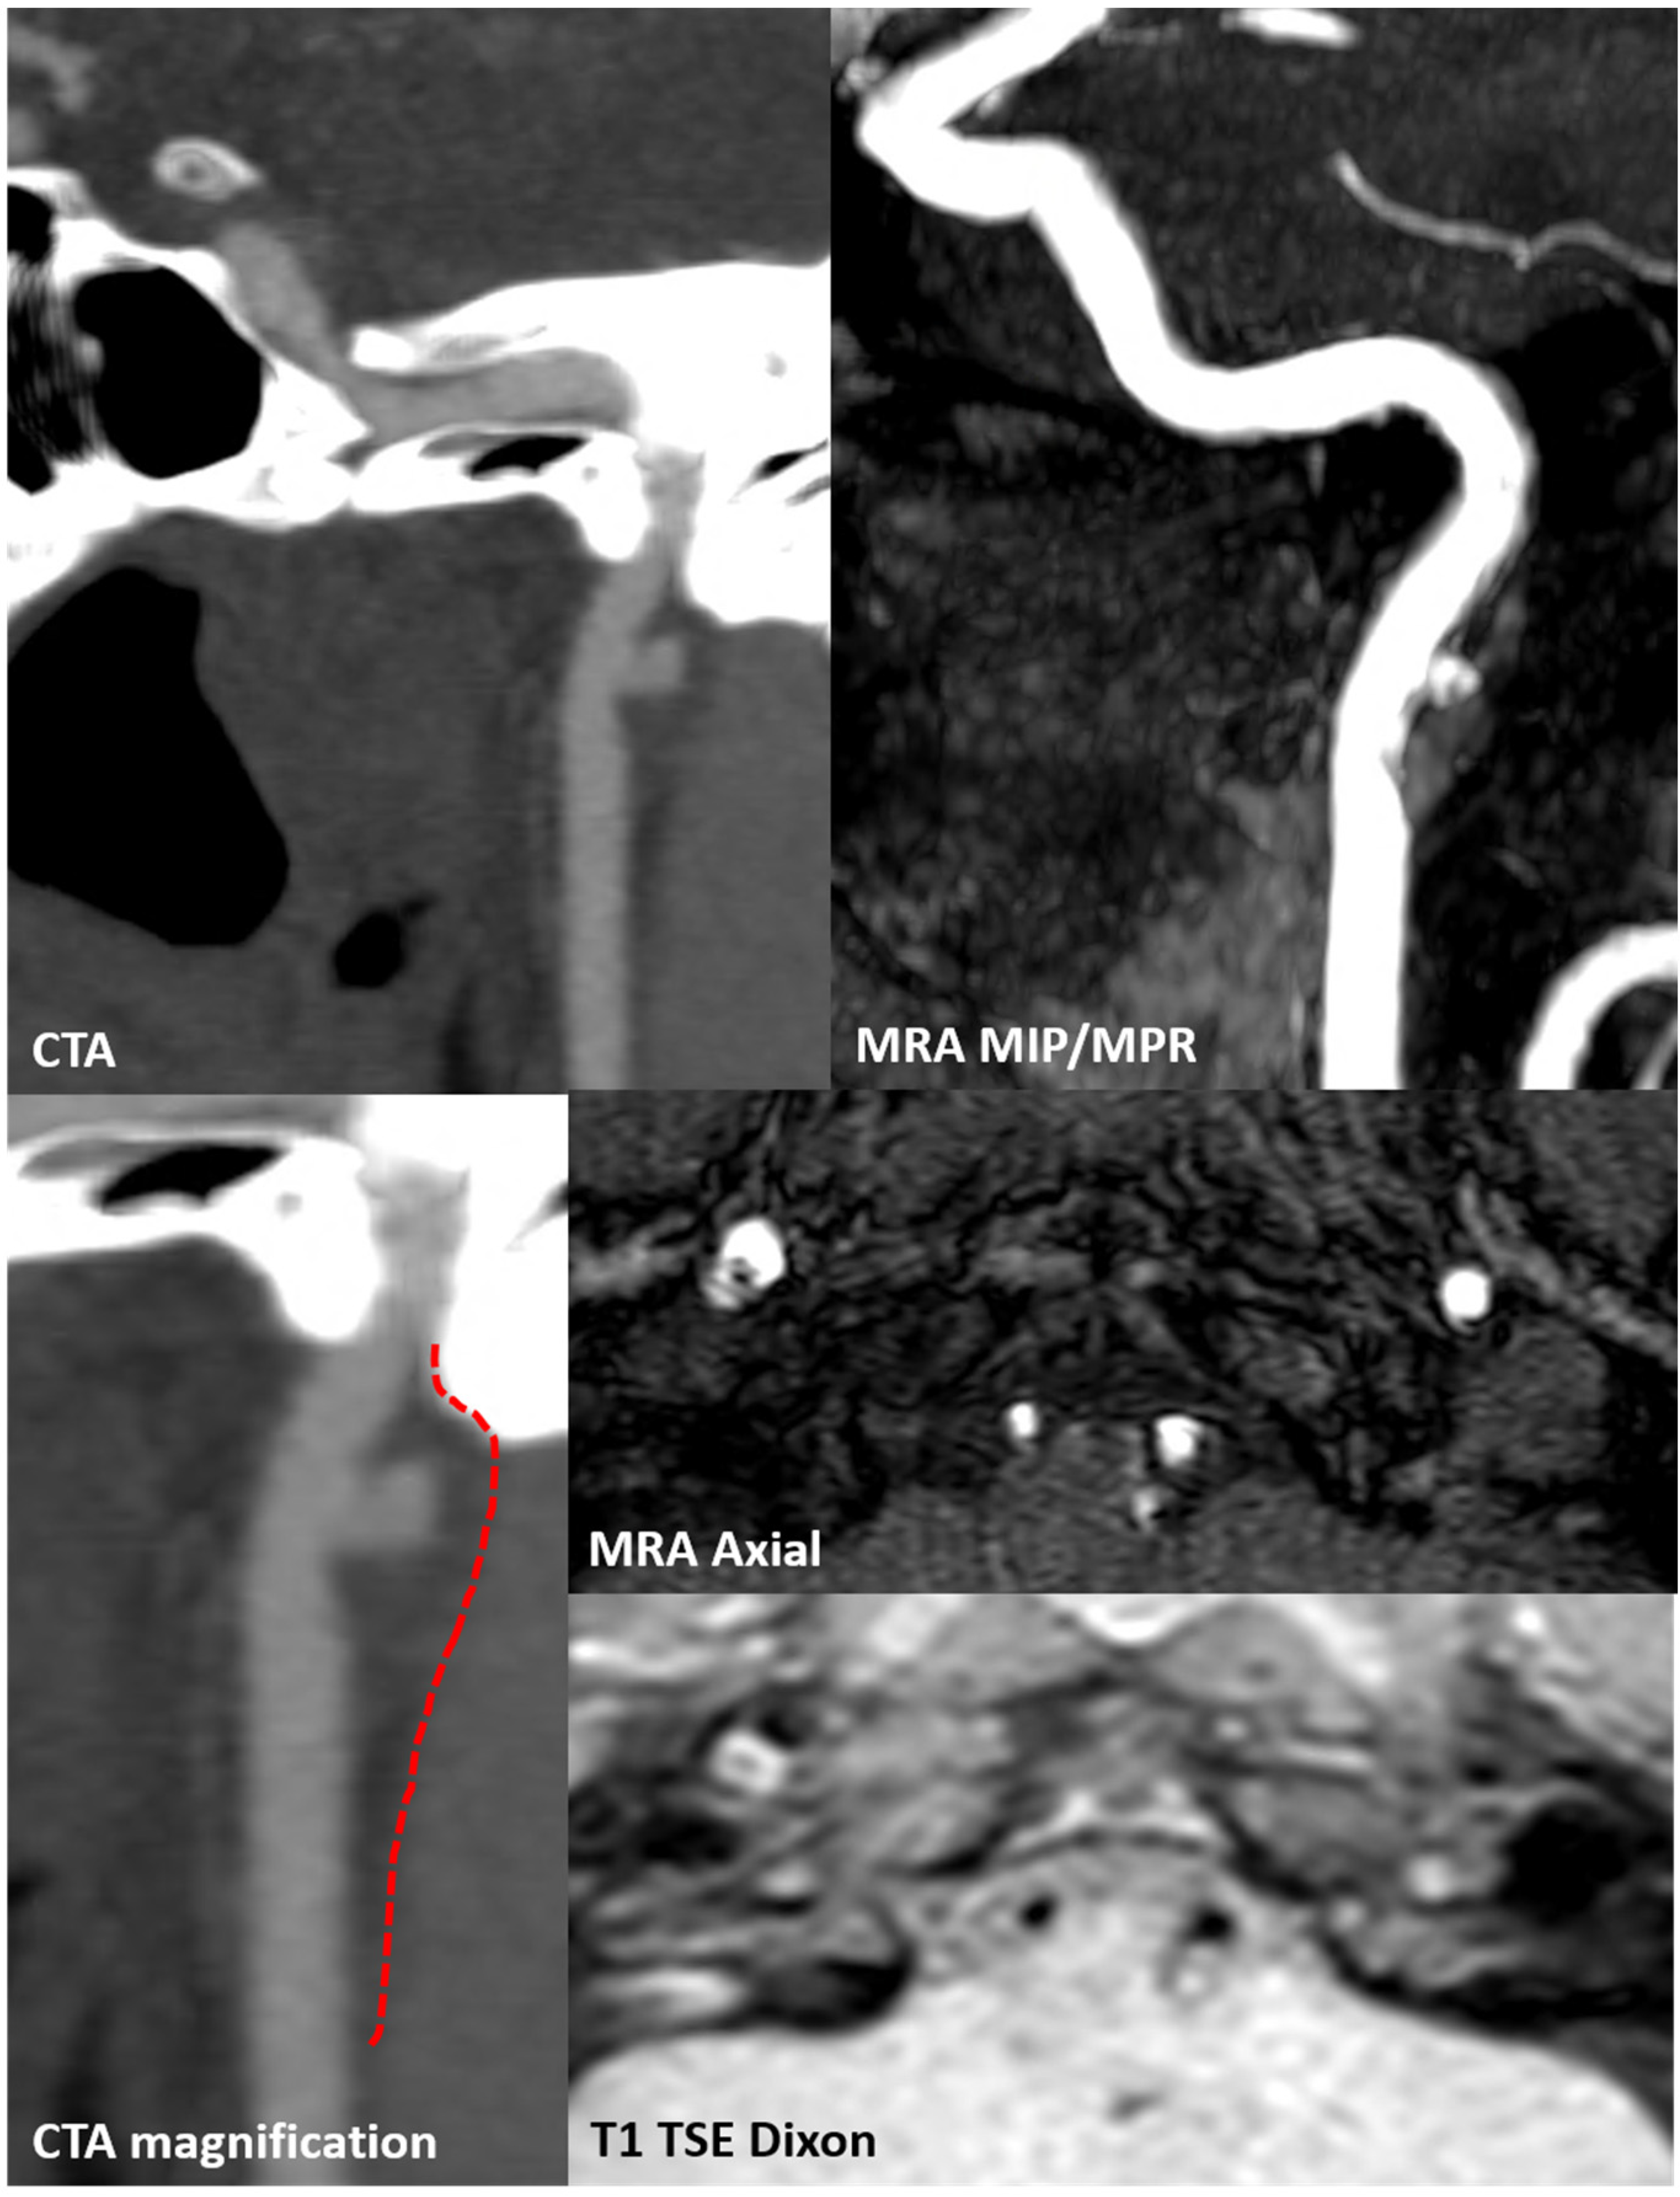

3.2. Case 2